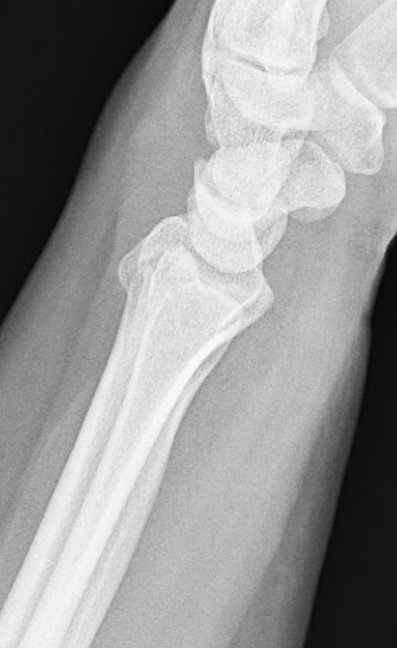

Given frx pattern and risk for concomitant SL injury (and ?SL widening), started scratching the ole’ noggin.

Couldn’t do dynamic (grip) view for injured side so we went for a contralateral comparison. Subtle differences if any…

Given the dominant-sided injury, radial and intemediate column injury, joint diastasis, possible SL injury, patient's age, we discussed surgery.

We decided that there was no better way to identify the SL injury other than with our eyeballs. So, scope/fix bone/address ligament.